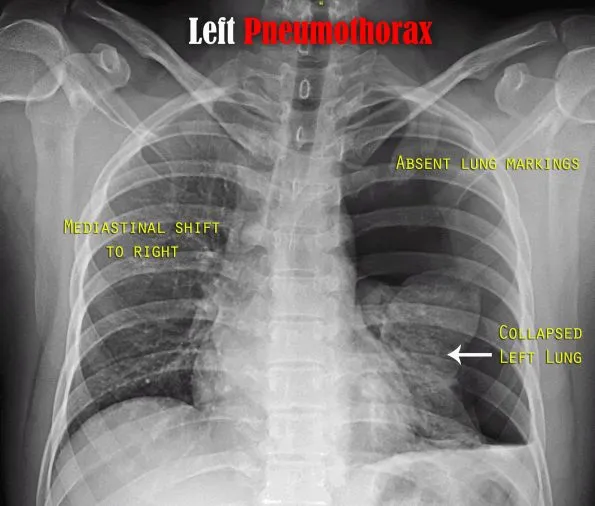

- CXR Signs:

- Visible visceral pleural line (sharp white line of the collapsed lung edge)

- Absent peripheral lung markings beyond the pleural line

- Tension Pneumothorax (EMERGENCY!):

- Mediastinal shift (contralateral, away from PTX)

- Diaphragmatic depression (ipsilateral)

- ↑ Hyperlucent hemithorax, widened intercostal spaces